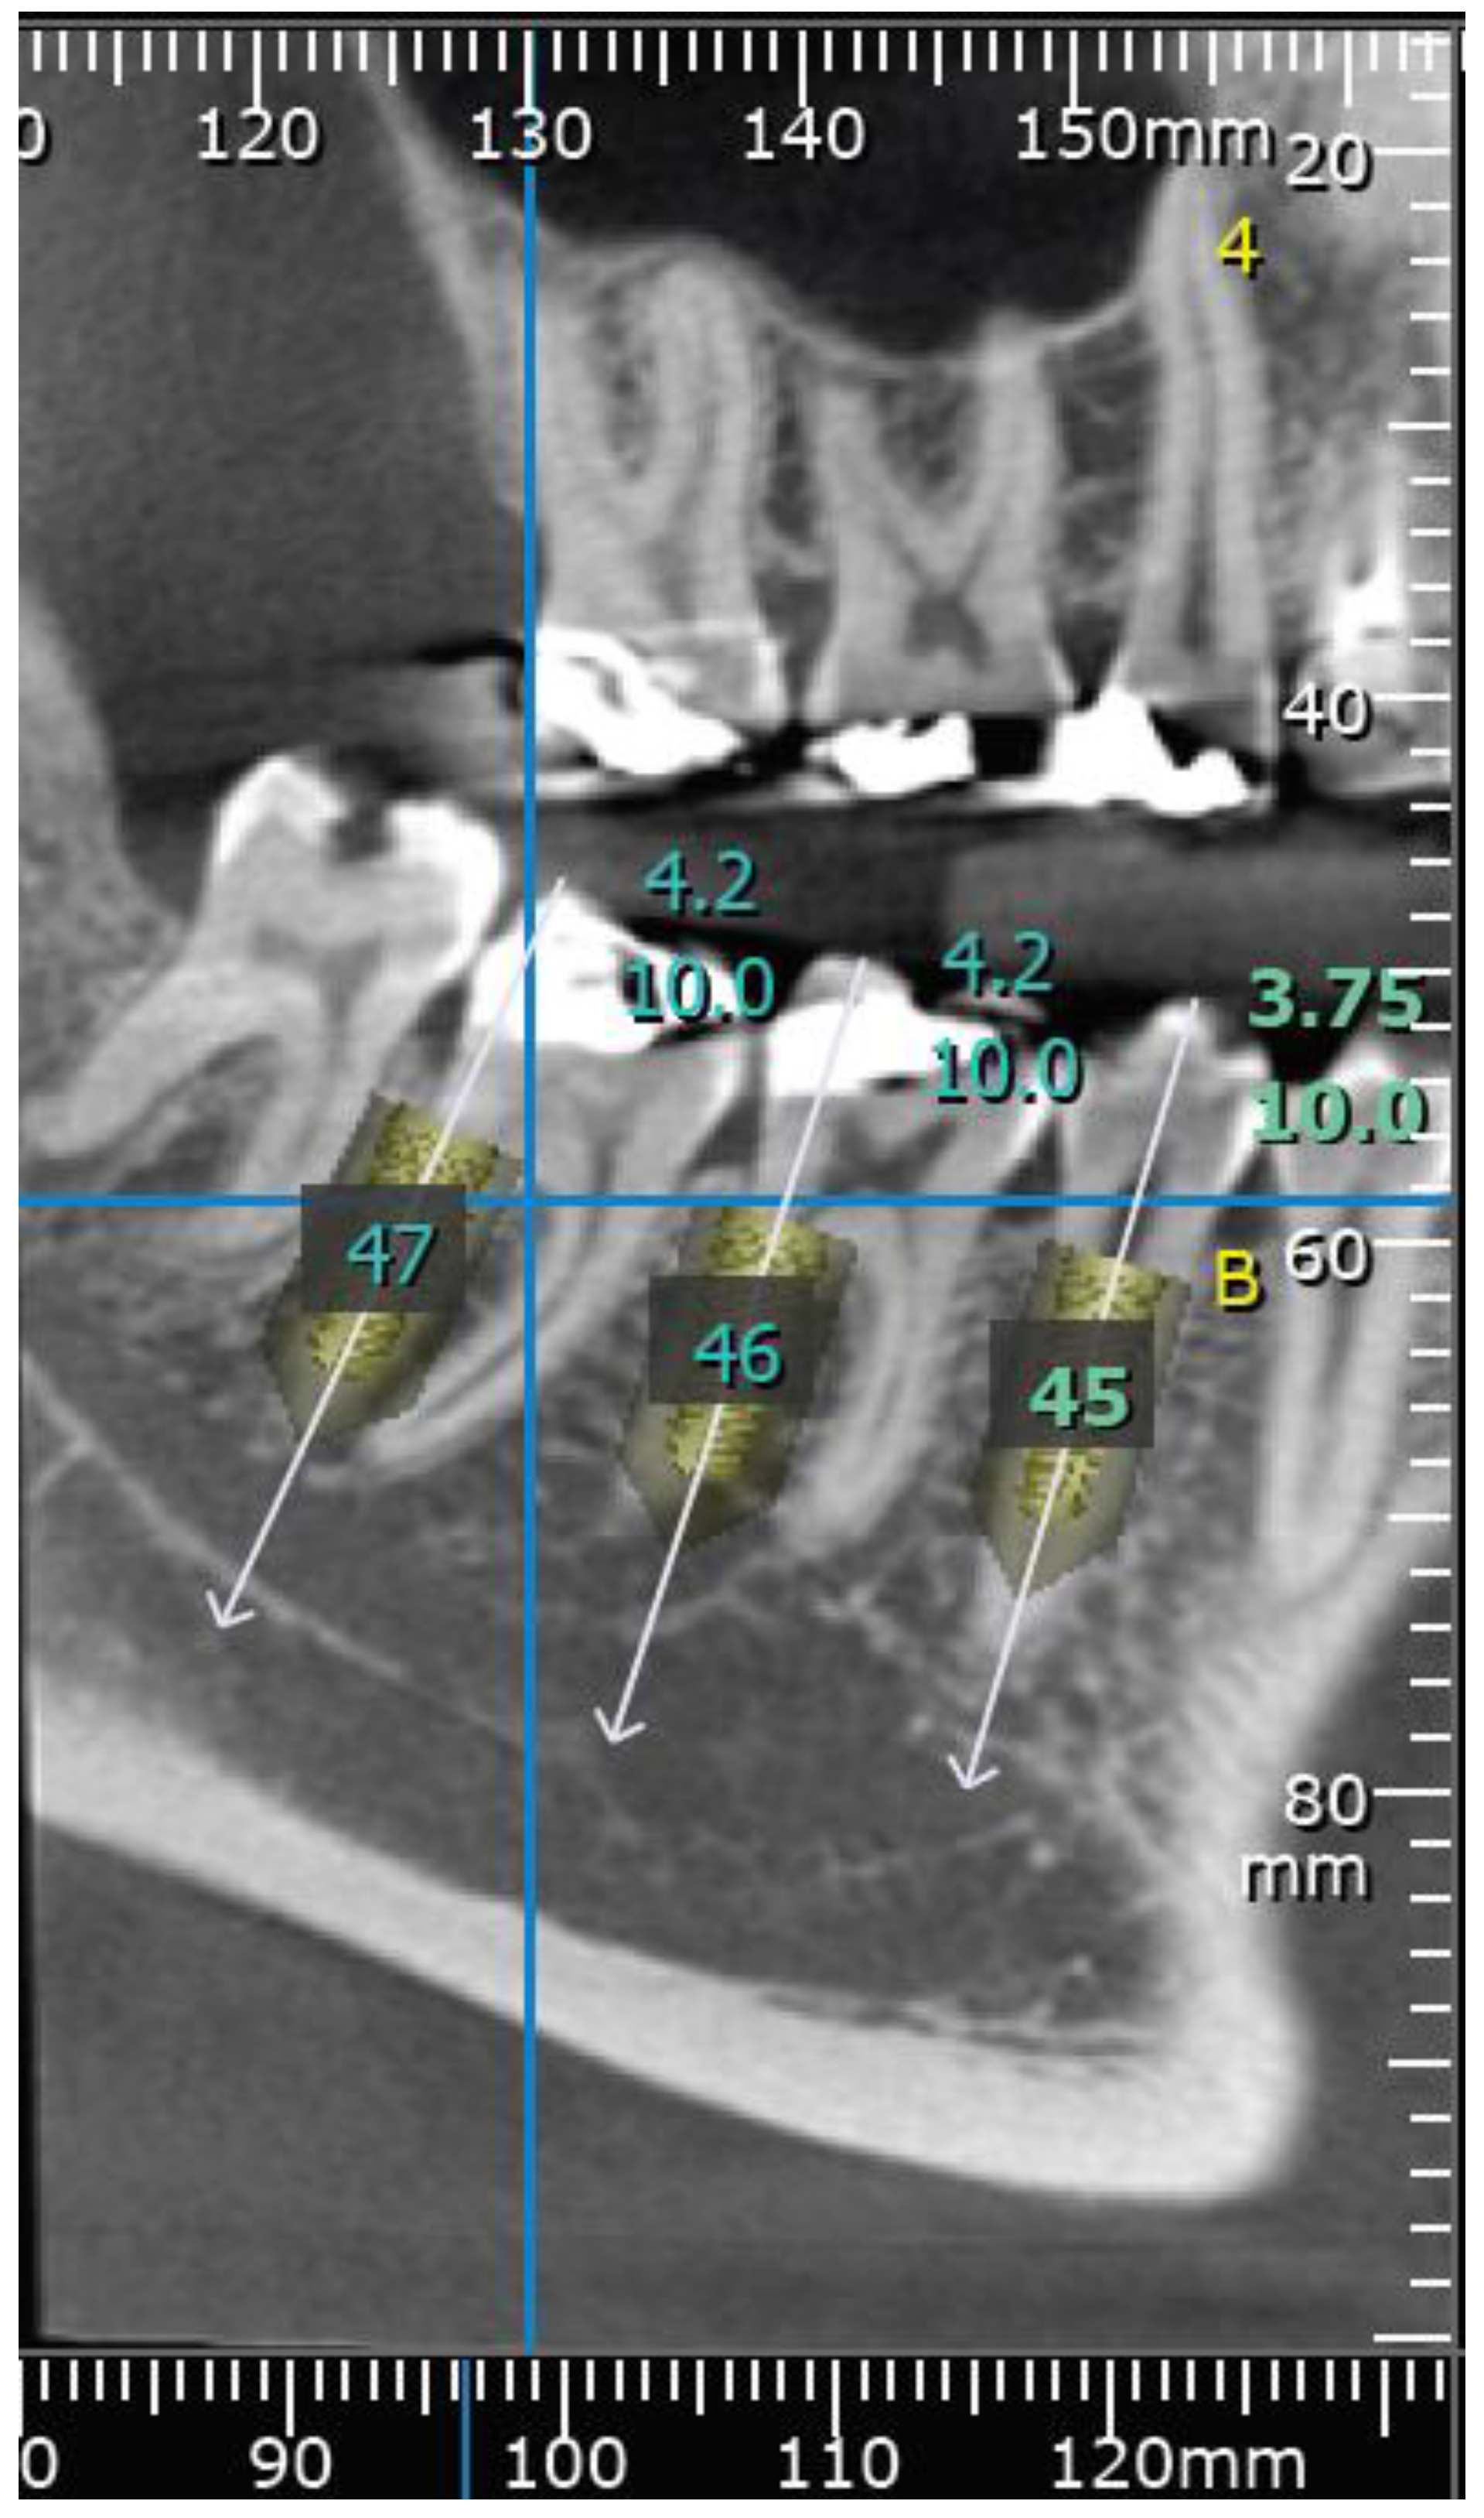

2. Materials and Methods

2.2. Procedure

2.3. Measurements